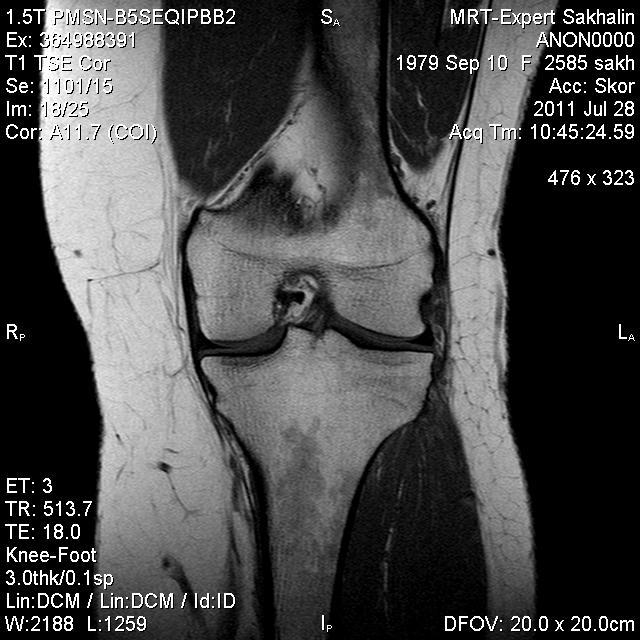

Коленный сустав

Подглядела случай у коллеги.

Что это может быть?

Не вижу криминала. А на что жалуется девушка?

P.S. В костях - это, скорее всего, резидуальный красный костный мозг.

Жалоба у всех одна на всех-болит.

участки гемопоэтического костного мозга